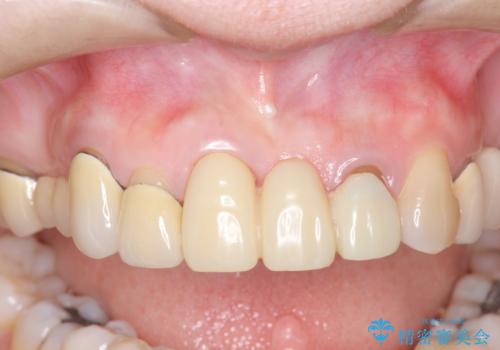

前歯ブリッジのやりかえ

- 前歯の審美障害、見た目の改善を希望され来院されました。

- 47万円(仮歯×3・ファイバーコア×2・ジルコニアクラウン×3 歯の挺出)費用は治療当時の料金となります